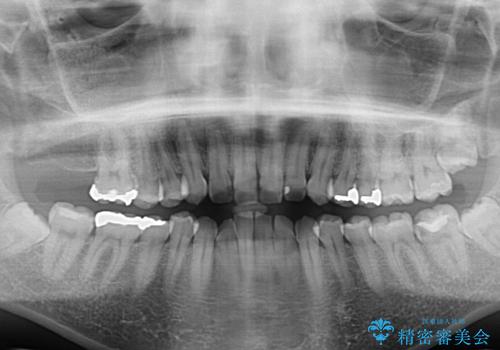

- 前歯のデコボコを気にして来院された患者様です。

主に下顎歯列全体の後方移動とIPR(歯と歯の間を削る)によってデコボコが解消するように設計し、インビザラインにより治療を行うこととしました。